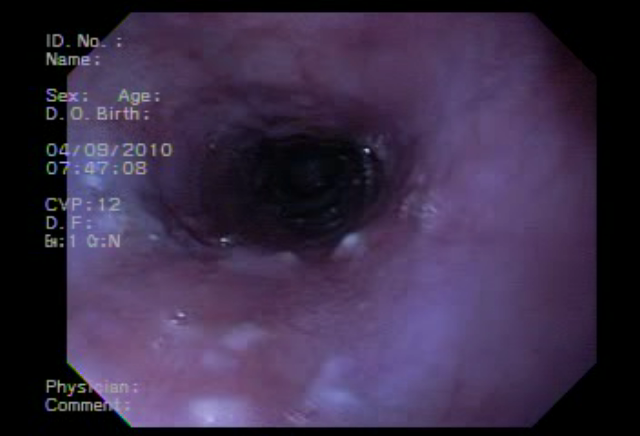

Endoscopía de tubo digestivo alto (Endoscopía superior, panendoscopía o esofagogastroduodenoscopía).

Es la observación del sistema digestivo superior: Esófago, Estómago y parte del Duodeno, utilizando un endoscopio flexible, ligero y delgado.